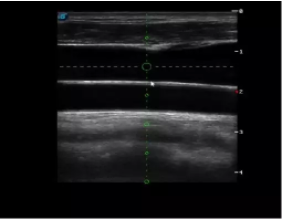

實(shí)時觀察穿刺針進(jìn)入血管的全過程,方便操作及較短的穿刺路徑,智能進(jìn)針尺寸提示,讓置管工作更加輕松,高效。

不同進(jìn)針路徑